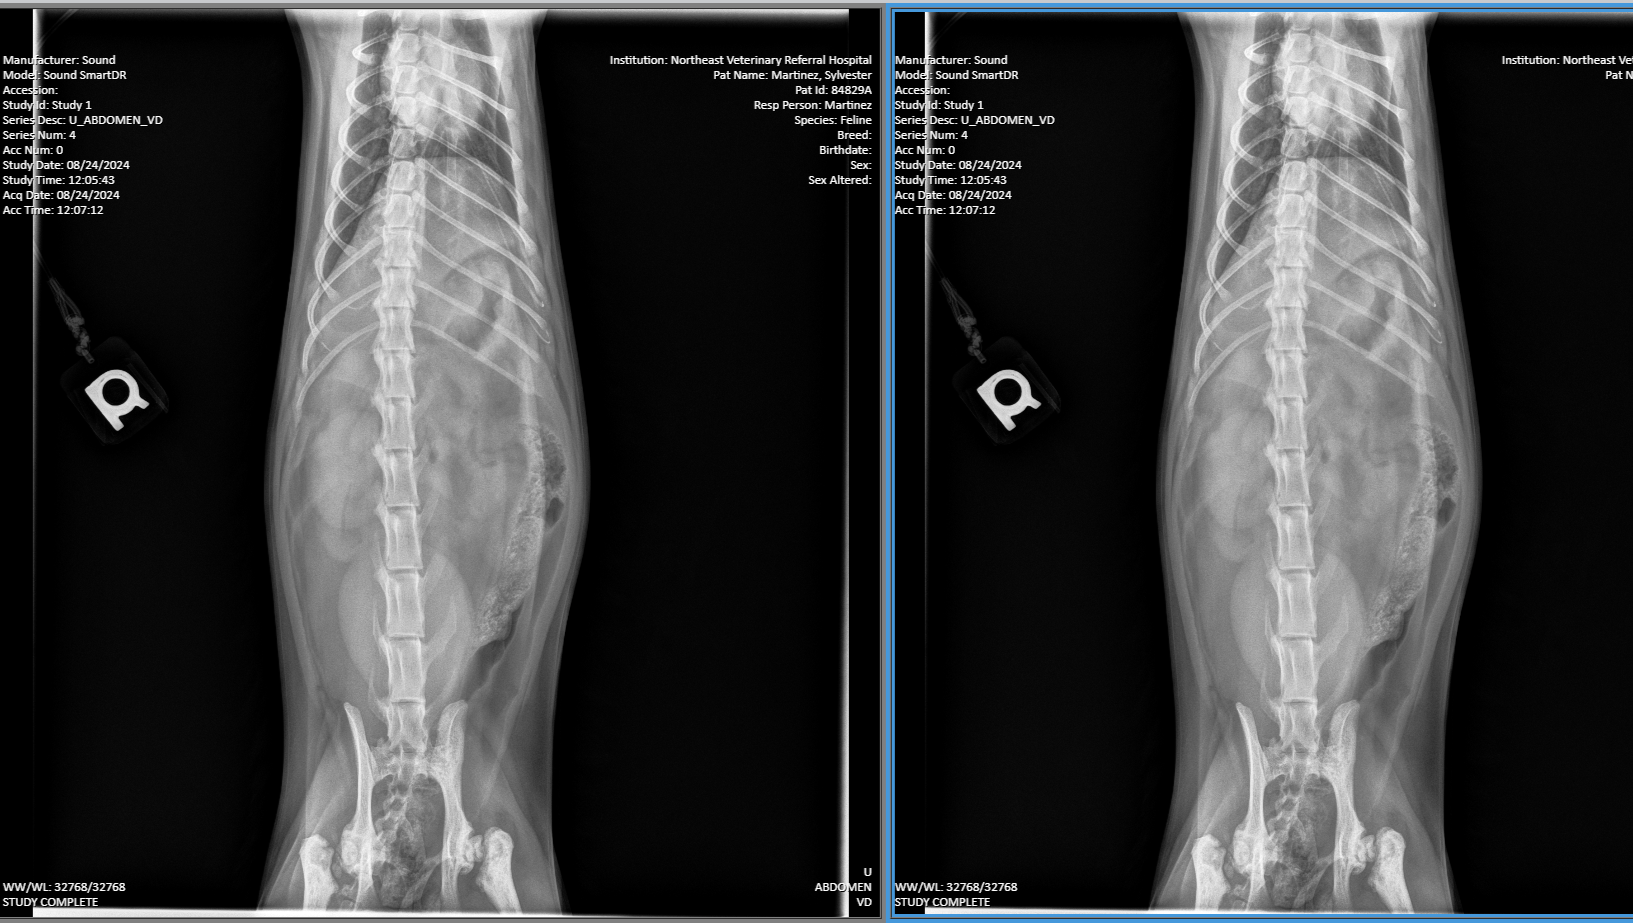

hello everyone, I have a 5-year-old cat that I brought to the emergency vet last August for constipation. they did an x-ray and they told me that he had a genetic hip dysplasia and that it wasn't that serious, fast forward to about a week ago, he was constipated again so I took him to the vet and they did another x-ray and come to find out that he was misdiagnosed the first time. it turns out that he has two broken hips that healed completely wrong. I got Sylvester when he was 6 months old from a very bad home. he was given to me with two eye infections, ear mites, and other things. I spoke to a surgeon and they said that they want to do surgery on him and that's going to cost about $3,000. I am struggling myself right now, but I will not give up on this cat. if you could find it in your heart to donate, me and Sylvester would greatly appreciate it thank you